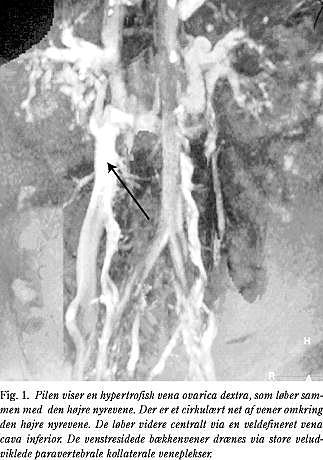

Der blev påbegyndt antikoagulations (AK)-behandling, og p-pillerne blev seponeret. Patienten fik høje kompressionsstrømper og blev mobiliseret i takt med, at rygsmerterne svandt i løbet af de næste dage. Ved udskrivelsen blev kompressionsstrømperne erstattet af knælange kompressionsstrømper klasse 3 (2). CT og UL-scanning 6 mdr. senere viste rekanalisering af venerne i bækkenet og i benene og VCIA blev igen bekræftet med en MR-scanning (Fig. 1 ). AK-behandlingen blev seponeret efter 8 mdr. To år efter symptomdebut anvendte patienten fortsat kompressionsstrømper og var velbefindende uden ødemer, venøs claudicatio eller recidiv af DVT.